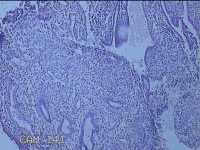

宫腔内容物

性别

女

年龄

47岁

临床诊断

1.异常子宫出血 2.慢性宫颈炎

一般病史

不规则阴道流血21天。

标本名称

大体所见

灰白暗红色不规则碎组织2.5x1.8x0.3cm一堆。

图1